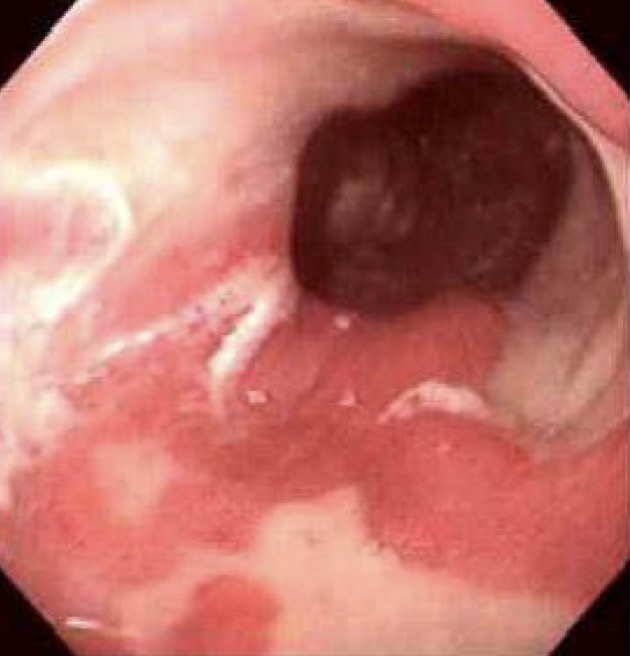

A- identify

B- describe

A- Columnar Metaplasia

B- This endoscopic view demonstrates Barrett

esophagus; areas of mucosal erythema of the

lower esophagus, with islands of normal pale esophageal squamous mucosa.